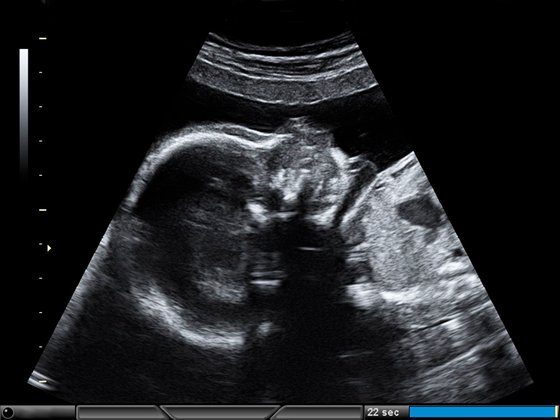

Wie wächst das Baby im 3. Trimester?

Oft ist jetzt bei Tritten durch die gespannte Babybauchdecke schon der Umriss der kleinen Füßchen zu erkennen. Vom Immunsystem bis zur Lungenreifung: Diese Entwicklungsschritte macht dein Baby in den letzten Wochen der Schwangerschaft. Möchtest du noch mehr Details zur Entwicklung des Babys wissen, klicke einfach auf die jeweilige Woche.

Endspurt: Die Entwicklung des Fötus im dritten Trimester als Tabelle

SSW | Entwicklung des Fötus | Durchschnittliche Größe Scheitel-Fersen-Länge | Durchschnitts-Gewicht |

Kommt das Kind in der 29. SSW zur Welt, liegt die Überlebenschance bei 90 %. | 38 cm | 1.150 g | |

Der Fötus bekommt über die Plazenta wichtige Abwehrstoffe. | 40 cm | 1.350 g | |

Dein Baby kann in SSW 31 riechen, tasten, schmecken, hören und sehen. | 41 cm | 1.500 g | |

Zwischen 15 und 20 h am Tag schläft dein Baby in der 32 SSW. | 42 cm | 1.700 g | |

Die Haut deines Kindes glättet sich nun in SSW 33 und verliert die Rötung. Sein Schlaf besteht zur Hälfte aus Tiefschlaf und einigen REM-Phasen. | 43 cm | 1.900 g | |

Das Gehirn entwickelt sich weiter. Und in der 34. SSW wird der Platz langsam etwas eng. | 44 cm | 2.100 g | |

Dein Baby erkennt jetzt um die 35. SSW herum vertraute Geräusche wieder. 99 % aller Babys überleben nun außerhalb des Mutterleibs. | 46 cm | 2.400 g | |

Möglicherweise bewegt sich der Fötus in SSW 36 weniger, die Körperbehaarung und die Käseschmiere werden ins Fruchtwasser abgegeben. | 47 cm | 2.600 g | |

Pro Tag nimmt dein Baby nun 28 Gramm zu. Das zentrale Nervensystem, die Lunge und der Verdauungstrakt sind in der 37. SSW ausgebildet. Die Nieren sind vollständig entwickelt. Die Leber übernimmt ebenfalls ihre Funktion. | 48 cm | 2.800-3.100 g | |

Nun kann es jeden Tag losgehen, das Baby ist in der 38. SSW fertig entwickelt. | 49 cm | 3.100 g | |

Tag für Tag lagert es in 39. SSW weiter Fettpolster an. | 50 cm | 3.250 g | |

Der Körper schüttet in der 40. SSW Hormone aus und zeigt so dem Baby, dass es sich auf den Weg machen kann. Normalerweise wiegen Babys bei der Geburt zwischen 2.800 und 4.000 Gramm. | 51 cm | 3.400 g |